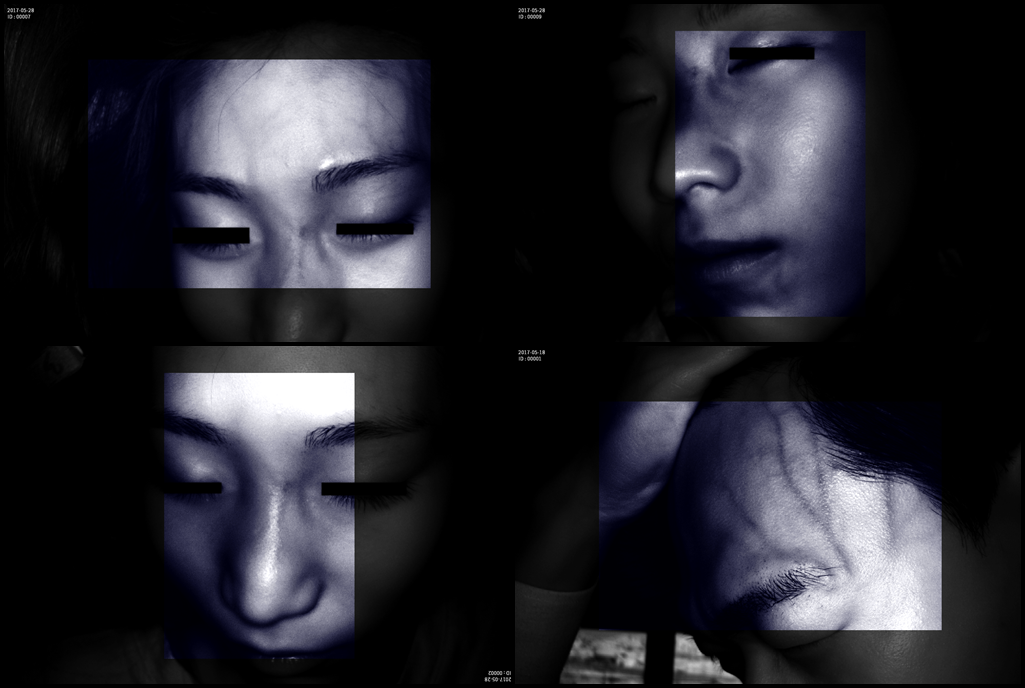

Grad mare de detecție a venelor greu vizibile până la 10 mm adâncime (inclusiv vene faciale)

Multiple aplicații de vizualizare vene atât la sugari cât și la pacienții obezi sau în urgențe indiferent de tonul de culoare a pielii